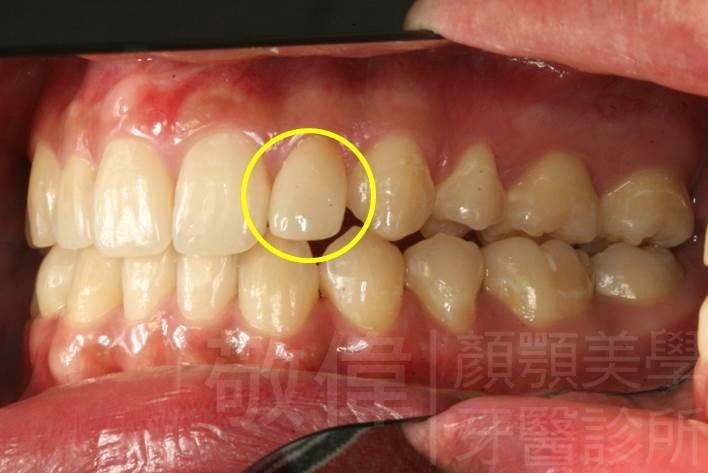

| 6 | 前牙美容 | 矯正+牙齦增補+晶鑽全瓷冠 | ||

| 7 | 前牙美容 | 矯正+晶鑽全瓷冠 | ||